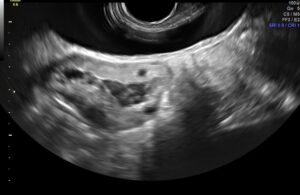

O diagnóstico do endometrioma de ovário geralmente é realizado sem dificuldades pelo ultrassom transvaginal.

Toda vez que um ultrassom simples identificou um endometrioma, é fundamental a complementação com um exame mais específico, como o ultrassom transvaginal com preparo intestinal.

Ultrassom transvaginal com preparo intestinal para o diagnóstico do endometrioma

O ultrassom transvaginal com preparo intestinal deve ser o exame de primeira linha para o diagnóstico e estadiamento da endometriose profunda e ovariana.